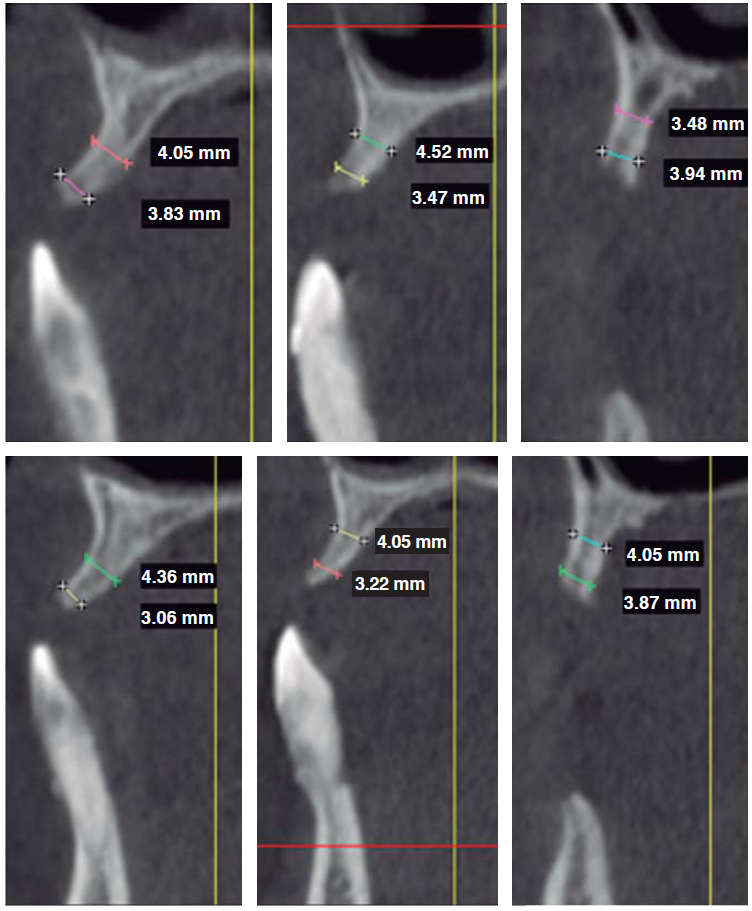

Se indicó una tomografía computarizada Cone Beam para evaluar la disponibilidad ósea remanente con finalidad de colocar implantes. A la evaluación se evidenció que en el maxilar superior, a pesar de la reabsorción ósea generalizada, se encontró cantidad ósea suficiente para la colocación de implantes en sentido coronoapical. Por el contrario, en sentido bucopalatino no se encontró la cantidad ósea suficiente para una colocación de implantes de manera convencional (Figura 2). Por tal motivo, este maxilar correspondería a la clase III de deformidades de los rebordes alveolares de Seibert, por lo cual es necesario realizar procedimientos quirúrgicos adicionales que permitan la colocación mínima de seis implantes.

Figura 2 La CBCT mostrando reabsorción ósea horizontal generalizada, aunque verticalmente, suficiente hueso encontrado en sentido apicocoronal. De izquierda a derecha superior: área de la pieza # 1.1, 1.2 y 1.4. De izquierda a derecha inferior: piezas # 2.1, 2.2 y 2.4.

En cuanto al maxilar inferior, se evidenció un defecto óseo que compromete los aspectos vestibulares y linguales del hueso remanente a nivel de la pieza 4.2. Sin embargo, se encontró cantidad ósea suficiente para la colocación de cuatro implantes en la zona interforamen.